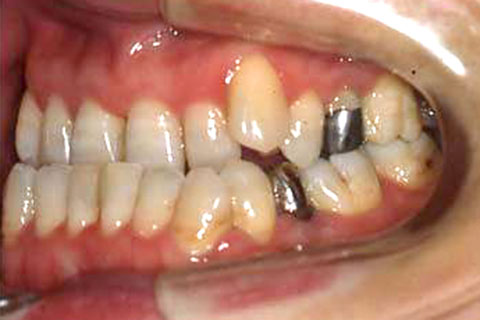

受け口(反対咬合)の症状

下あごが上あごより突出しているか、上あごが下あごより後退している状態で、咬み合わせが逆になっているので反対咬合ともいいます。お子様の場合、受け口(反対咬合)を放置していると、成長期において下あごが過大に成長し悪化しますので、出来る限り早い時期に治療することをおすすめします。受け口(反対咬合)は見た目の問題だけでなく顎の動きを制限し、将来的に顎の痛み(顎関節症)を引き起こす場合があります。また、お子様の場合は、正常な上顎の成長を阻害する可能性があります。

受け口(反対咬合)の症例